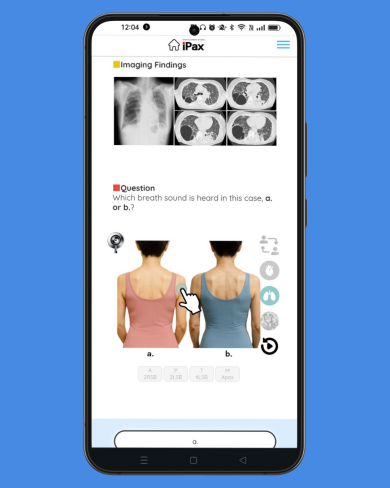

June 18 – Question on Crackles Today’s question focuses on crackles. The question includes a description of the characteristics of the crackling sound. Please listen to the two MP3 audio files and choose the one that matches the description. (June 18, 2025)